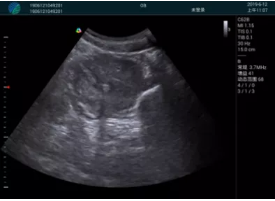

病例一:

清晰顯示孕囊,通過(guò)軟件包計(jì)算孕齡7w+6d

M20實(shí)時(shí)引導(dǎo),術(shù)中清晰顯示孕囊被破壞和抽吸針的過(guò)程,清晰顯示吸引針

抽吸結(jié)束后縱切子宮,孕囊已被完全抽吸,未見(jiàn)明顯殘留

橫切子宮,發(fā)現(xiàn)右側(cè)宮腔靠近宮角處有少許脫模樣殘留

M20引導(dǎo)下,抽吸針找到右側(cè)宮角處再次清掃

二次抽吸后再次進(jìn)行超聲檢查,宮腔未見(jiàn)殘留,宮腔線(xiàn)清晰顯示

超聲引導(dǎo)下可視化人流是技術(shù)安全性的保障,一般對(duì)人流術(shù)設(shè)備預(yù)算不高,M20具備婦產(chǎn)科軟件包,且穿透力圖像質(zhì)量好,既滿(mǎn)足人流引導(dǎo)需要,也可用于床旁超聲的需求。